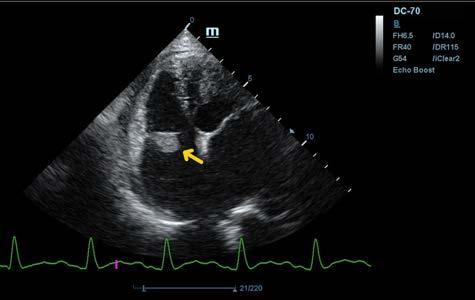

Se realiza ecocardiografía en la cual observamos engrosamiento de la válvula mitral (Fig. 2) y alteración de la estructura de las cámaras cardiacas: ratio atrio izquierdo/aorta 2,25 (Fig. 3), diámetro de ventrículo izquierdo en diástole normalizado (DVIdn) 1,98, patrón de flujo transmitral pseudonormal con velocidad máxima de onda E de 1,7 m/s, tiempo de relajación

M. López,1 V. Fernández,2 J. Engel3 1Servicio de cardiología y diagnóstico por imagen. 2Servicio de cirugía. Laclinicaveterinaria. c/Marroquina 26. 28030 Madrid. 3Servicio de cardiología. ANICURA-Benipeixcar Hospital Veterinario. Avinguda de la Constitució 68, bajo izq. 46009 Valencia. ANICURA-San Francisco Hospital Veterinario. c/ Sant Francesc 65. 12500 Vinaròs (Castelló). ANICURA-San Vicente Hospital Veterinario. c/ Veterinario Manuel Isidro Rodríguez García 17. 03690 San Vicente del Raspeig (Alicante). Figura 1. Radiografía lateral de tórax en la que se observa cardiomegalia generalizada, VHS 15. Patrón alveolar intersticial compatible con edema pulmonar. Patrón vascular mixto y patrón bronquial en lóbulos caudales, compatible con bronquitis crónica, mineralización por degeneración senil.

isovolumétrica (TRIV) acortado, 30 ms, y regurgitación mitral de hasta 4,6 m/s. En la ecocardiografía se observa también una masa hiperecoica bien definida de hasta 7 x 4,3 cm de diámetro en la base aórtica (Fig. 4) y un acúmulo de derrame pericárdico leve que no permite la pericardiocentesis. Además, se detecta un nódulo hiperecoico redondeado de 1,56 cm de diámetro en la válvula tricúspide (Fig. 5).

Figura 2. Ecocardiografía en corte paraesternal izquierdo eje largo, de 4 cámaras en la que se observa engrosamiento de la válvula mitral (flecha). Figura 3. Ecocardiografía en corte paraesternal derecho eje corto en base de corazón, visualizando ratio atrio izquierdo/aorta aumentado. Figura 4. Ecocardiografía en corte paraesternal izquierdo en base de corazón, en las que se observa la estructura hiperecoica y heterogénea junto a la aorta en un corte de la lesión transversal (A) y otro longitudinal (B). Compatible con neoplasia. A B Figura 5. Ecocardiografía en corte paraesternal izquierdo eje largo, optimizada para válvula tricúspide en la que se observa estructura hiperecoica.